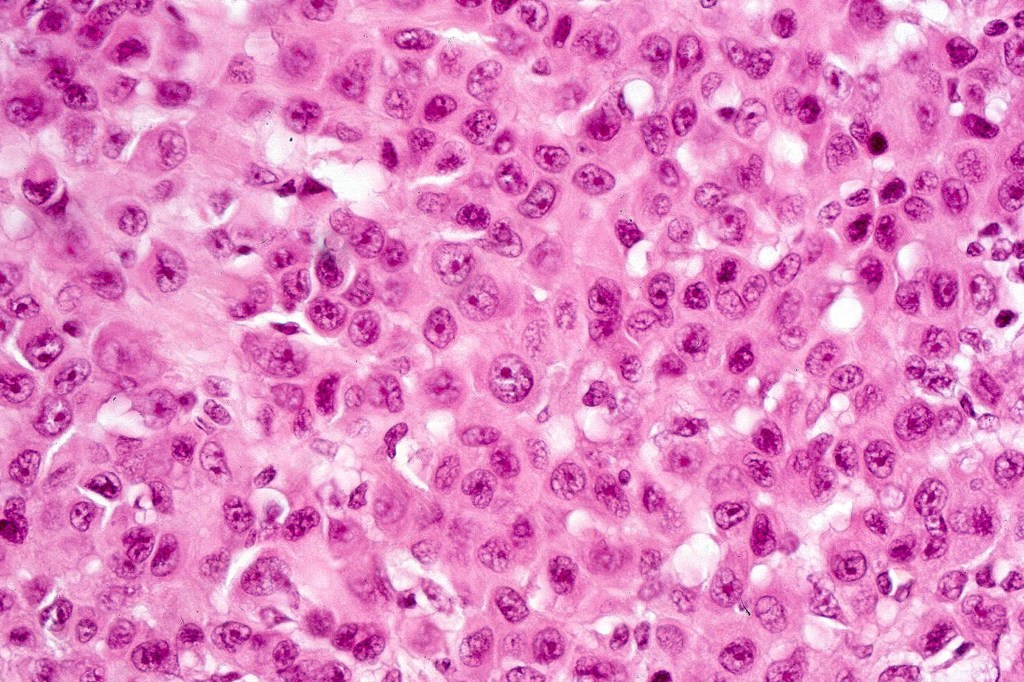

Melanoma arising in a congenital nevus

•Although the vast majority arise in giant forms, they may be encountered in smaller lesions & can be present at birth

•Develop in the dermal component

•Typical melanoma, nevoid melanoma, small cell melanoma, pleomorphic/anaplastic melanoma, melanoma with heterologous differentiation & malignant nerve sheath-like melanoma.

This melanoma arose in a small congenital nevus of the scalp. It metastasized widely. Varying features in different fields.